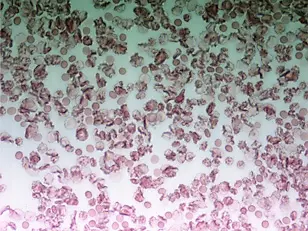

People whose blood clots more easily than normal are more often affected by cancer. Scientists at the German Cancer Research Center (Deutsches Krebsforschungszentrum, DKFZ) have discovered that a number of variants of clotting factor genes have an influence on bowel cancer risk. They found out that carriers of a particular gene variant of clotting factor V have a bowel cancer risk that is six times higher than people who do not have this gene variant. This study is an important basis for finding out whether and for whom drugs which affect blood clotting may be useful to prevent bowel cancer.

Back in the mid 19th century, a French doctor, Armand Trousseau, discovered a connection between cancer and thrombosis – the formation of often dangerous blood clots that can lead to venous occlusion. Today it is known that cancer and its treatment change blood flow properties and thus promote the formation of clots. However, clots do not only occur as a side effect and consequence of cancer, but, vice versa, an increased blood clotting tendency may also be associated with an elevated cancer risk.

About twelve different blood proteins called clotting factors interact in a coordinated manner in the blood clotting (coagulation) process. In the same way as hemophilia (decreased blood clotting) is inherited, genes also play a role in an increased clotting tendency (thrombophilia): There are well studied gene variants (polymorphisms) of a number of clotting factors which are associated with an increased or decreased clotting tendency. Between two and five percent of the population carry such genetic variants.